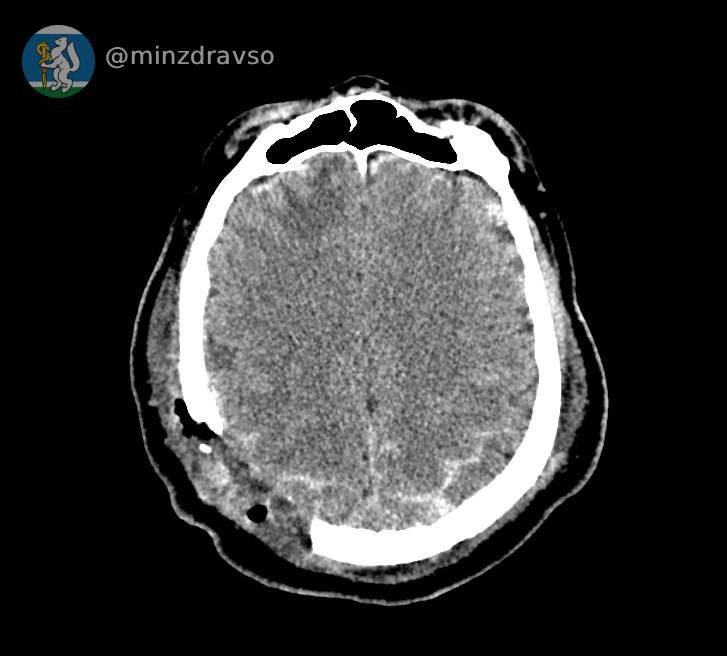

В Свердловской области благодаря усилиям врачей из Серова, Нижнего Тагила и Екатеринбурга удалось спасти 57-летнего мужчину, пострадавшего от удара по голове стрелой строительного крана.

Как рассказали на информационном портале регионального Минздрава «Здоровье уральцев», у мужчины была тяжелейшая черепно-мозговая травма. Любой из осколков черепа, повредивших мозг, мог стать причиной смерти.

Провести компьютерную томографию, чтобы понять, как именно раскололся череп, и стабилизировать состояние пациента оперативно смогли врачи Серова. Затем, после консультации с профильными специалистами из Екатеринбурга, мужчину экстренно перевезли в больницу Нижнего Тагила, где его уже ждала операционная бригада: врачи удалили осколки костей и восстановили целостность твёрдой мозговой оболочки.

Фото: министерство здравоохранения Свердловской области